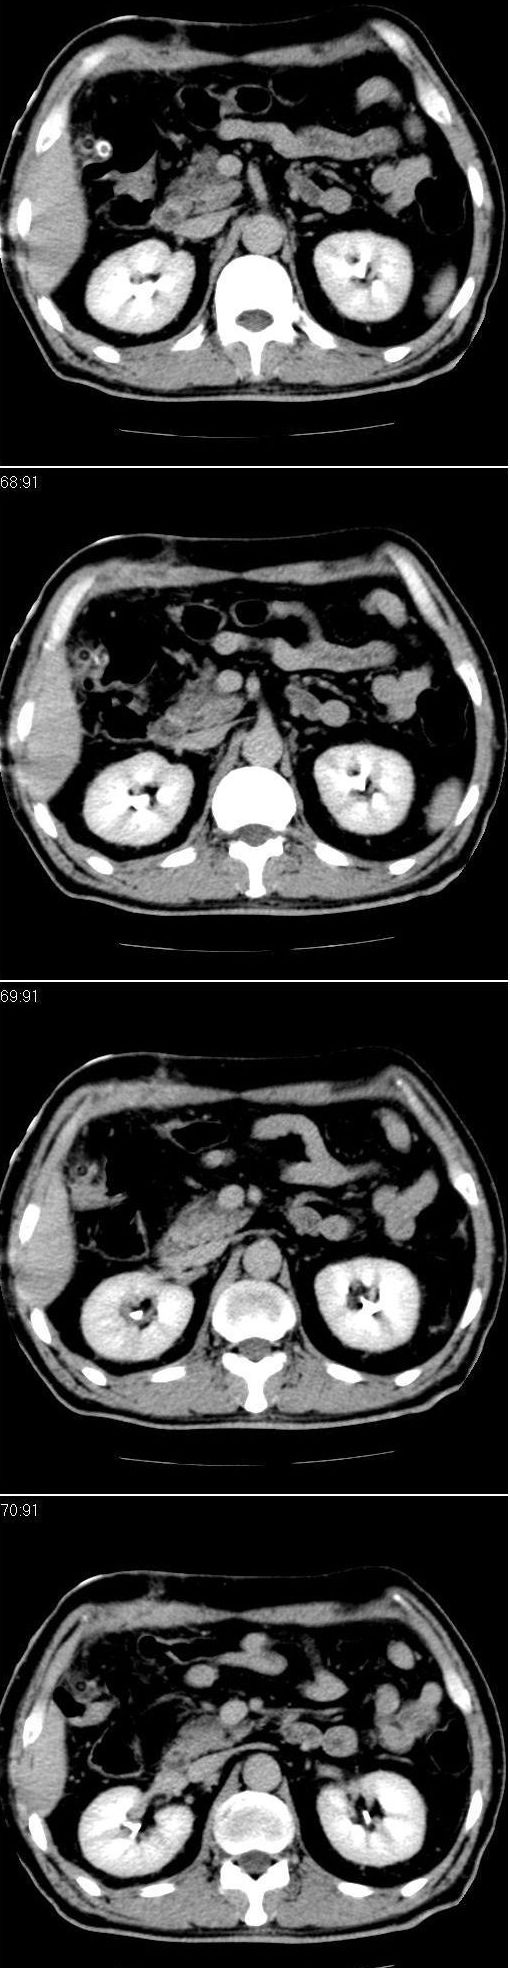

男,57岁。因胆结石阻塞性黄疸入院。这是胆囊切除术后的照片,看看此片到底有什么问题。

胆总管有没有问题,尤其是肝门附近的胆总管?

肝门附近的胆总管轻度扩张 请楼主复习术前片

肝内外胆管轻度扩张,胆囊窝内见引流管考虑胆囊切除术后改变.胃窦部软组织似增厚,建议胃镜检查.

在手术切除胆囊的过程中,发现肝门部胆总管恶性占位,因为家属不同意手术,没有切除,能看出来么?

现有资料很难说,薄层可能清楚些,如临床不提供,易诊断为术后改变。

不是楼主提醒还真看不出来,肝内胆管扩张。略显僵硬。

肝内外胆管轻度扩张。楼主提示左右肝管合汇区域壁稍厚。胆总管末段壁似也稍厚有轻度强化。就现有资料诊断难。